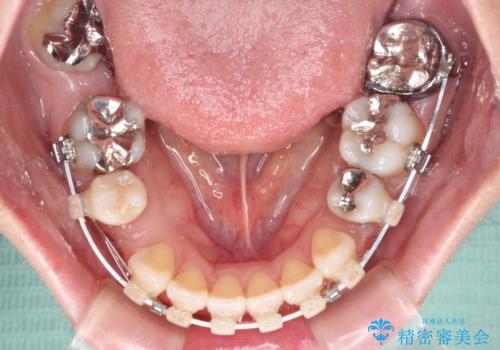

出っ歯と奥歯の欠損 ワイヤー矯正とインプラント治療

- 口元の突出感と奥歯の欠損を気にして来院された患者様です。

口元の突出感改善には、上下左右の第一小臼歯4本を抜歯し、奥歯の欠損部には矯正治療の途中でインプランを埋入していくこととしました。

矯正治療の後半にインプラント埋入を行うことで、トータルの治療期間を短縮することができました。